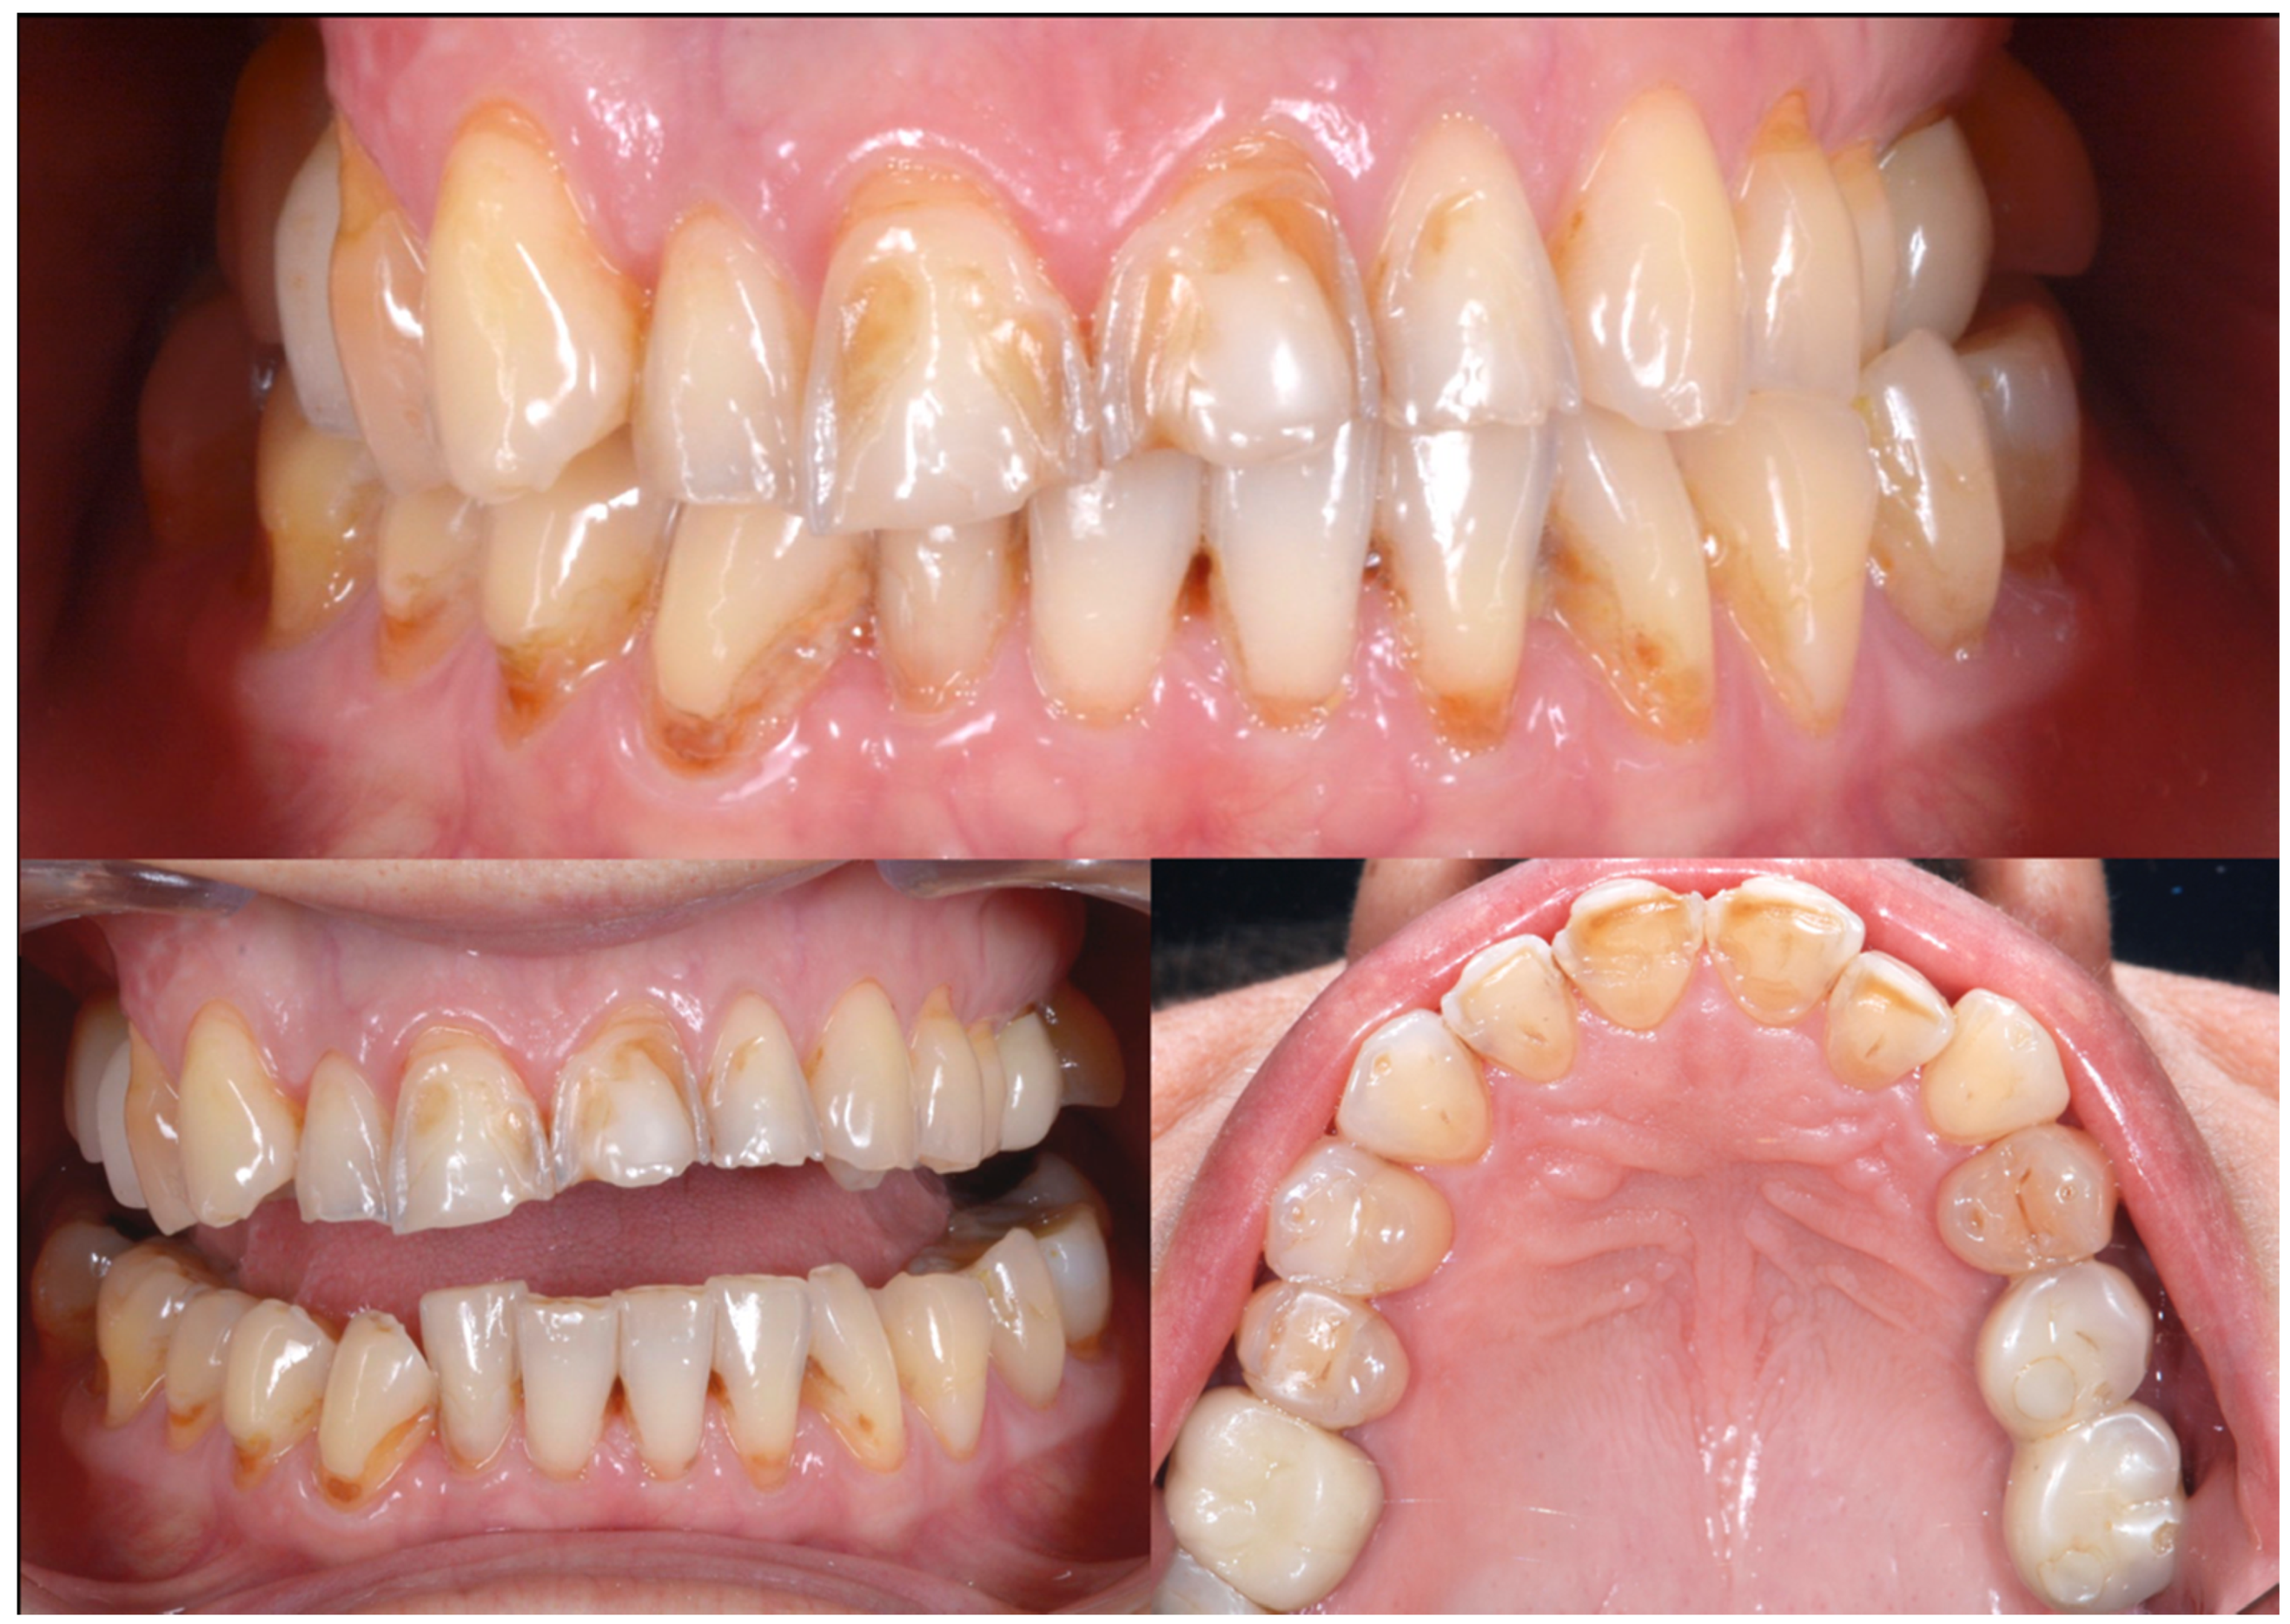

2.2. Clinical Example